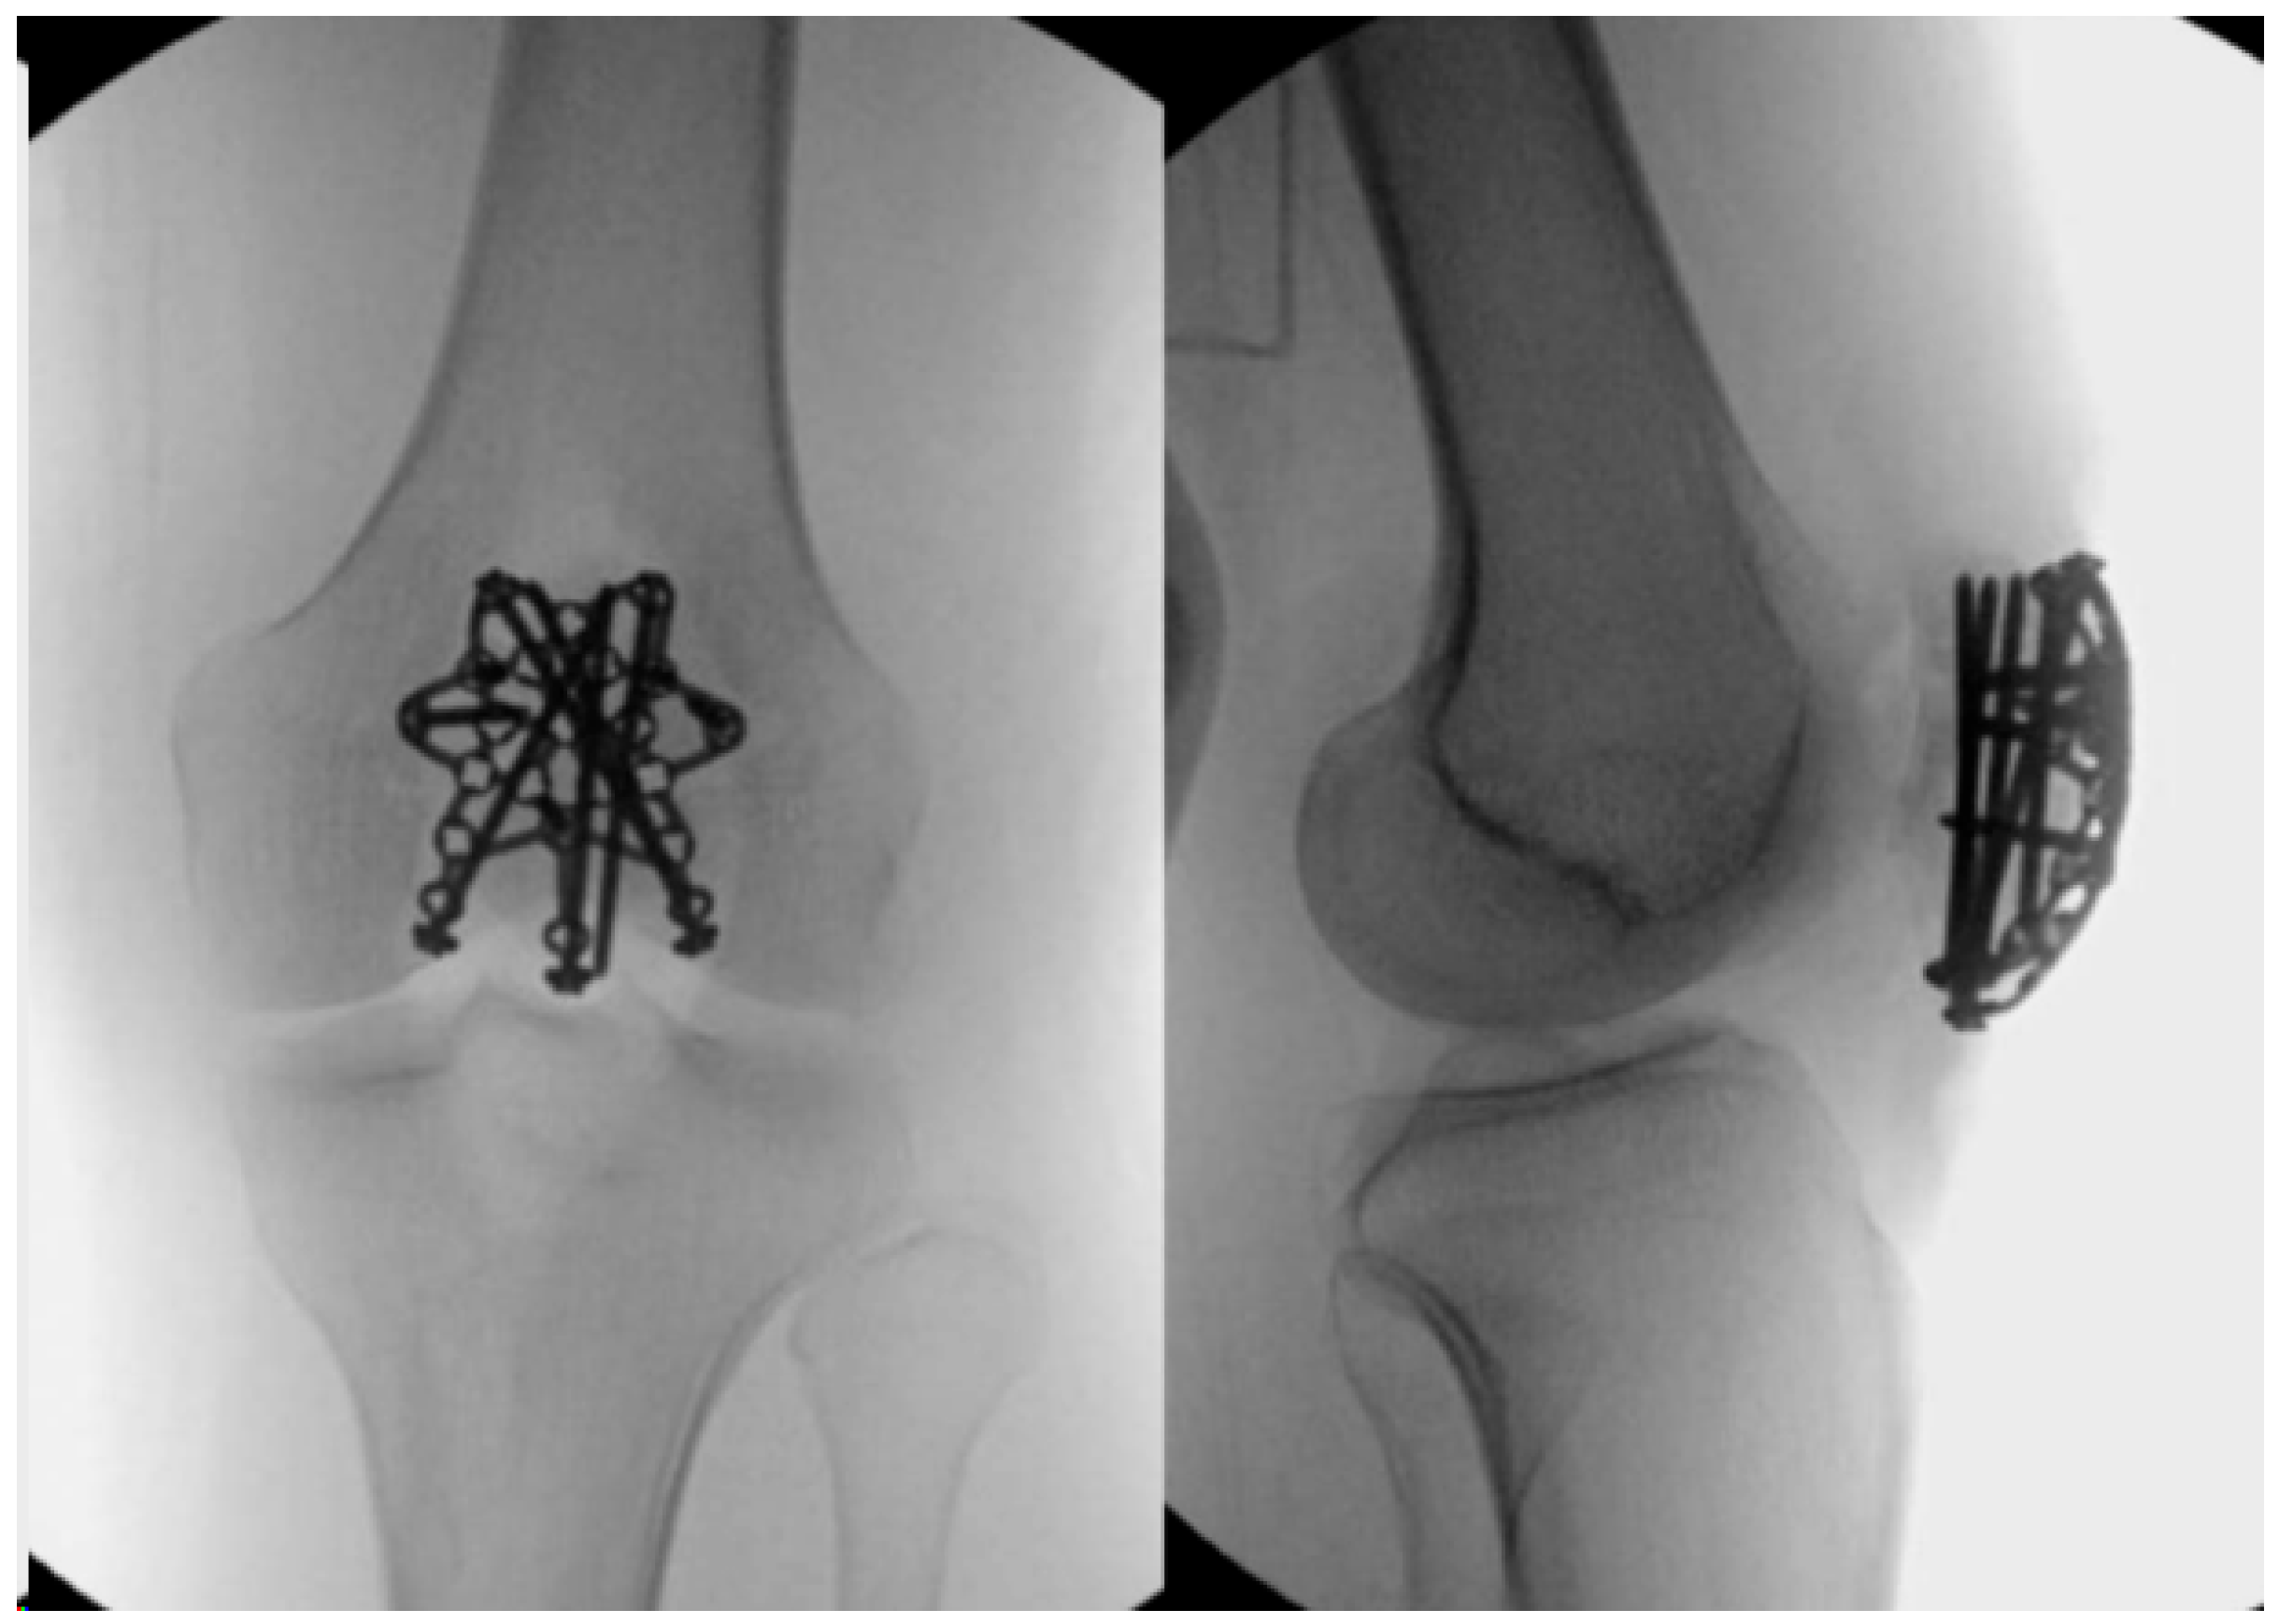

2.3. Tension Band Wire

2.5. Locking Plates